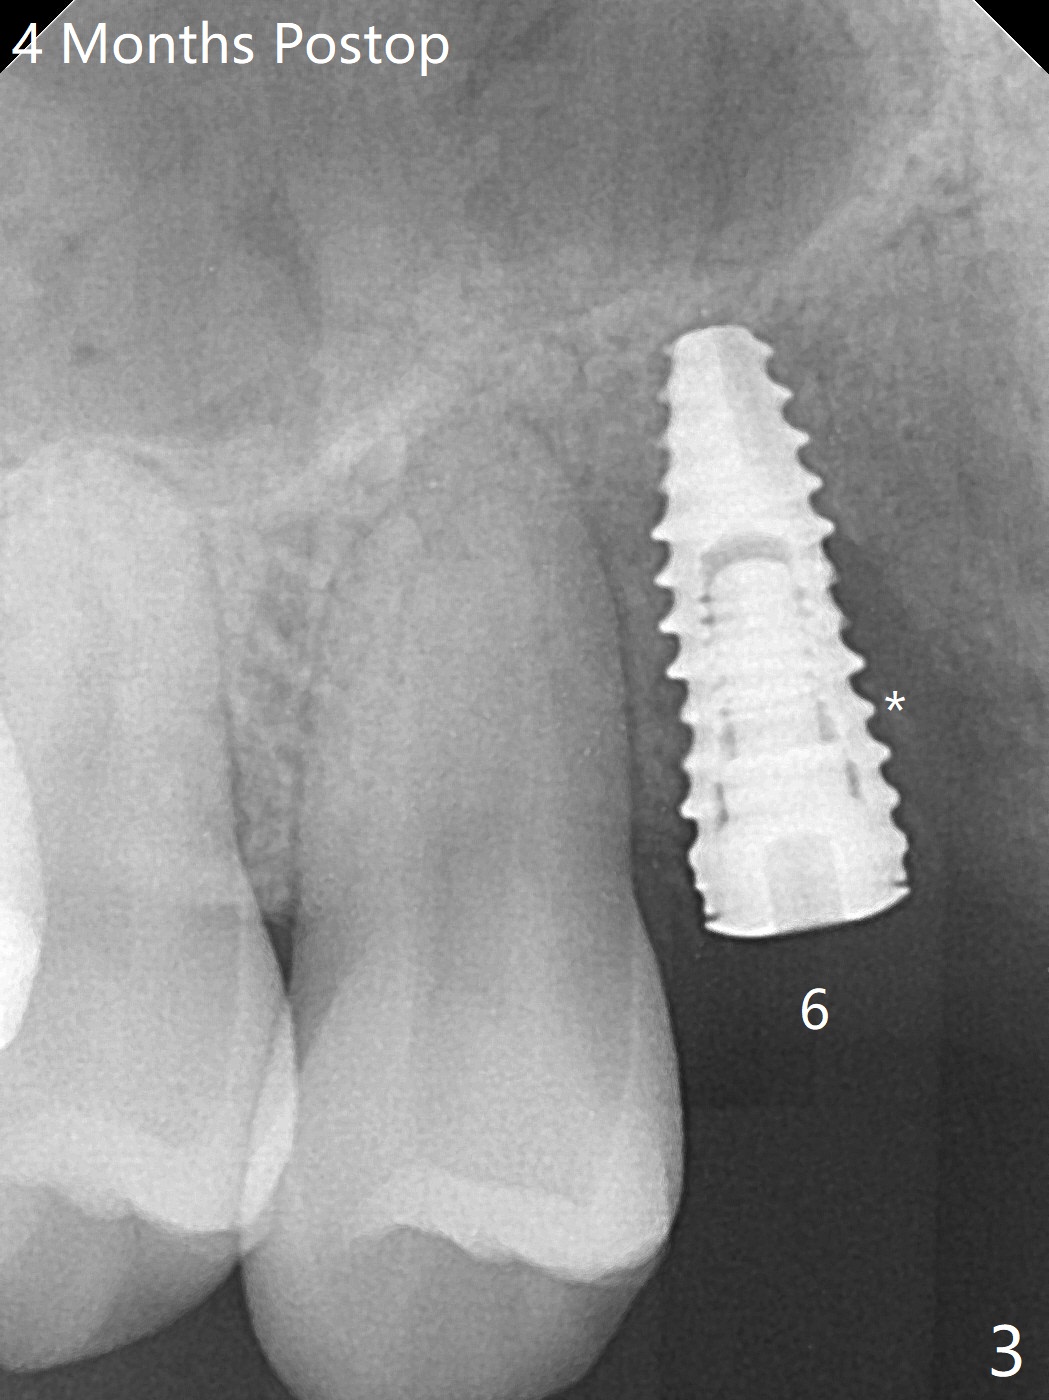

18岁男从外州大学回来,无症状,但是6号牙(右上尖牙)颊侧瘘道(图一,二(角化龈充分(箭头))),根尖片显示植体近中骨吸收(图三:*),而对侧植体仿佛骨整合(图四)。患侧切开后发现植体颊侧暴露,松动。拔除后骨缺损由粘性骨粉修复(图七,九:*),覆盖PRF膜(图七:P)和带钛网(图九:^)不可吸收膜(图五-七),后者用两个小钉子固定(图六(腭侧),七(颊侧),九),使用新的刀片和一个特殊尖头剥离器在颊侧骨膜下相当广泛分离,使用PTFE缝线,粘膜下水平褥式缝合之后(图八:箭头),多个垂直间断缝合,两个乳头垂直褥式缝合。术后一周伤口没有裂开,术后疼痛肿胀已经消退(图十)。术后十八天牙槽嵴仿佛比对侧还要宽(图十一,三与图十二,四(取模)对比)。术后5.5个月伤口没有裂开,牙槽骨,角化龈宽(图十六),与钛网和两个小钉子固定有关(图十五,十七)。CT显示牙槽骨只能容纳2.5或者3.0毫米植体(图十八)。11号牙植体牙冠粘固后没有骨质吸收(图十九),其实10,11号牙颊侧骨板隆起(图二十至二十二),而6植体失败,颊侧骨板吸收,甚至累及5号牙(图十七)。